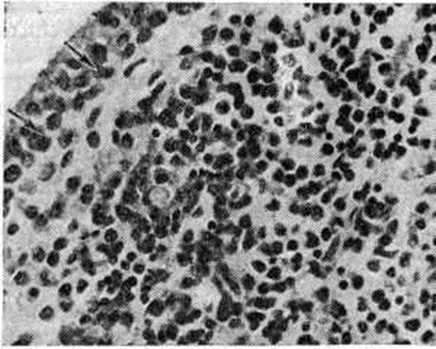

Рис. 4.

Микропрепарат синовиальной оболочки сустава при ревматоидном артрите: диффузная лимфоидно-плазмоцитарная инфильтрация и пролиферация синовиоцитов (указаны стрелками); окраска гематоксилин-эозином; ×200.

В гистологический картине синовита выделяют следующие изменения: 1) поражение сосудов микроциркуляторного русла; 2) гиперплазию и гипертрофию синовиальных клеток; 3) воспалительную клеточную инфильтрацию; 4) разрастание грануляционной ткани, склероз, липоматоз синовиальной собственной пластинки. Повышается проницаемость стенок сосудов микроциркуляторного русла, сопровождающаяся выходом фибринозного экссудата и образованием очагов фибриноида в синовиальной собственной пластинке и фибриноподобных наложений на поверхности синовиальной оболочки. Иммуноморфологически в очагах фибриноида и в фибриноподобных наложениях выявляются фибрин, иммуноглобулины (G, А, М) и С3-фракция комплемента. При обострении воспаления постоянно отмечается продуктивный или продуктивно-деструктивный васкулит с фиксацией в сосудистой стенке иммуноглобулинов и комплемента. В глубоких слоях синовиальной оболочки (смотри полный свод знаний) изредка определяются ревматоидные узелки — небольшие участки фибриноидного некроза, окружённые макрофагами и лимфоцитами. В 80% случаев встречается гиперплазия и гипертрофия синовиоцитов с характерным палисадообразным их расположением (рисунок 2). С помощью электронно-микроскопического исследования обнаружено, что гипертрофия синовиоцитов происходит за счёт гиперплазии их органелл, особенно зернистой эндоплазматической сети, полисом, аппарата Гольджи и лизосом (рисунок 3). В гиперплазии ворсинчатого слоя синовиальной оболочки участвуют синовиоциты всех трёх типов (А, В и С). На ранних стадиях обострения воспаления клеточная инфильтрация в синовиальной оболочке скудная, представлена лимфоцитами, макрофагами и полиморфно-ядерными лейкоцитами. В дальнейшем отмечается лимфоидно-плазмоцитарная инфильтрация (рисунок 4), иногда с формированием лимфоидных фолликулов. Параллельно при иммунофлюоресцентном изучении Т и В-лимфоцитов синовиальной оболочки при Ревматоидный артрит Банкхерст (A. D. Bankhurst) с соавторами (1976) выявил преобладание Т-лимфоцитов. В синовиальной оболочке отмечается значительная пролиферация фибробластов. В синовиальной собственной пластинке и фиброзном слое наблюдается разрастание грануляционной ткани с исходом в склероз (смотри полный свод знаний) и липоматоз (смотри полный свод знаний).